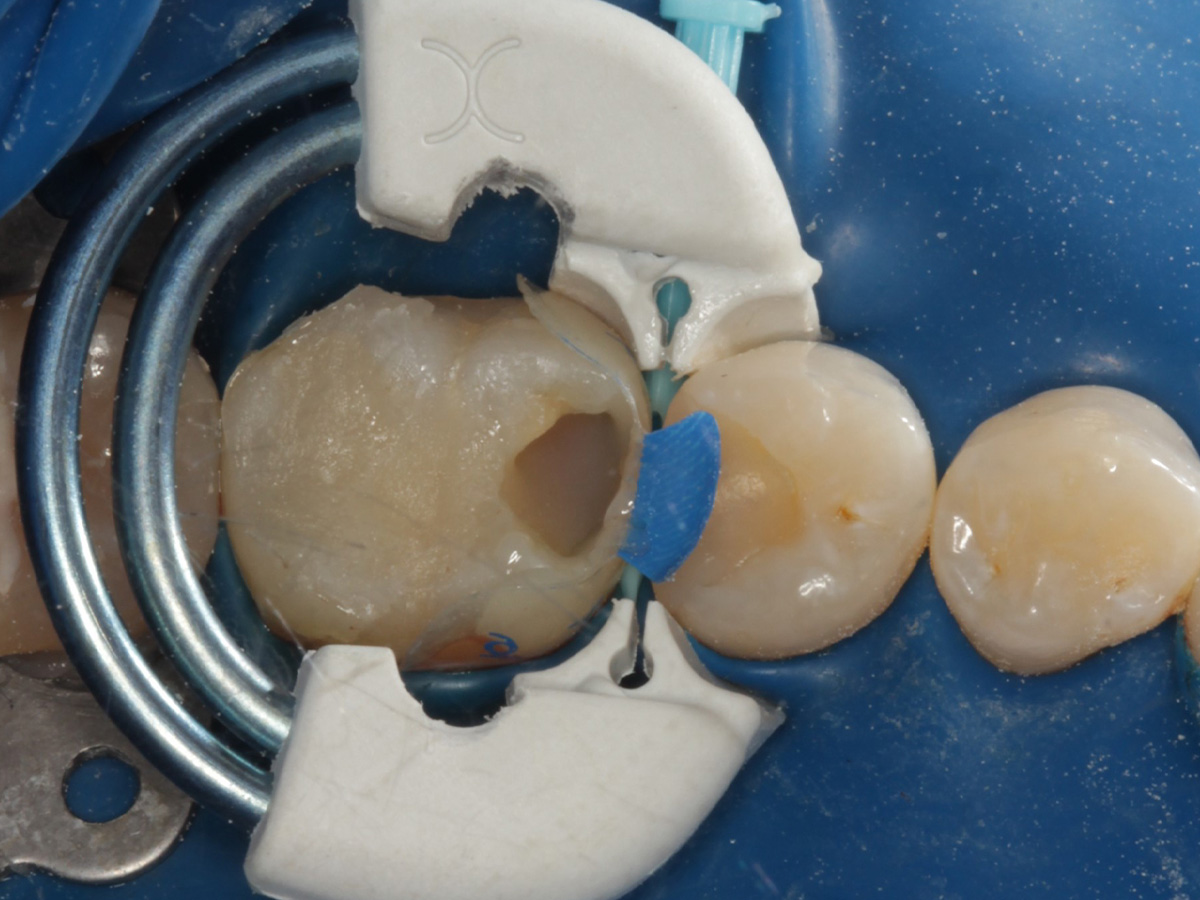

Abbildung 3

Schutz des Nachbarzahnes und des Kofferdams mit wiederverwandter Bioclear Biofit Matrize (gereinigt und sterilisiert); Separation zur Applikation der Matrize mit Heidemannspatel